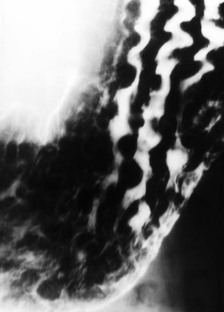

Gastric erosions or aphthous ulcers are superficial ulcerations that do not penetrate the muscularis mucosa. They usually appear as small, shallow collections of barium 1–2 mm in diameter surrounded by a radiolucent rim of oedema. These are called ‘complete’ or ‘varioliform’ erosions (Fig. 27-6A).